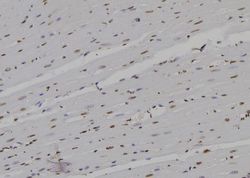

LS-C806267 IHC

Method:

Other validation